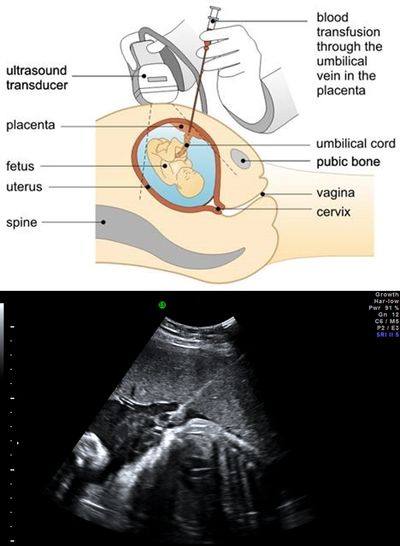

FBS is usually performed as early as 18 weeks onwards in pregnancy.

Under local anaesthesia and constant ultrasound guidance, a fine needle is passed through the mother’s abdomen to obtain a sample of the fetal blood from the umbilical cord close to the placental cord insertion avoiding sampling from the free loop of cord. Alternative sites for FBs include Intrahepatic portion of the umbilical vein in the fetus. The procedure usually takes 10-15 minutes and the fetal heartbeat is shown to the mother at the end of the procedure.

Following fetal blood sampling, the same needle entry could be used for intrauterine fetal blood transfusion and injecting medications as part of fetal therapy.